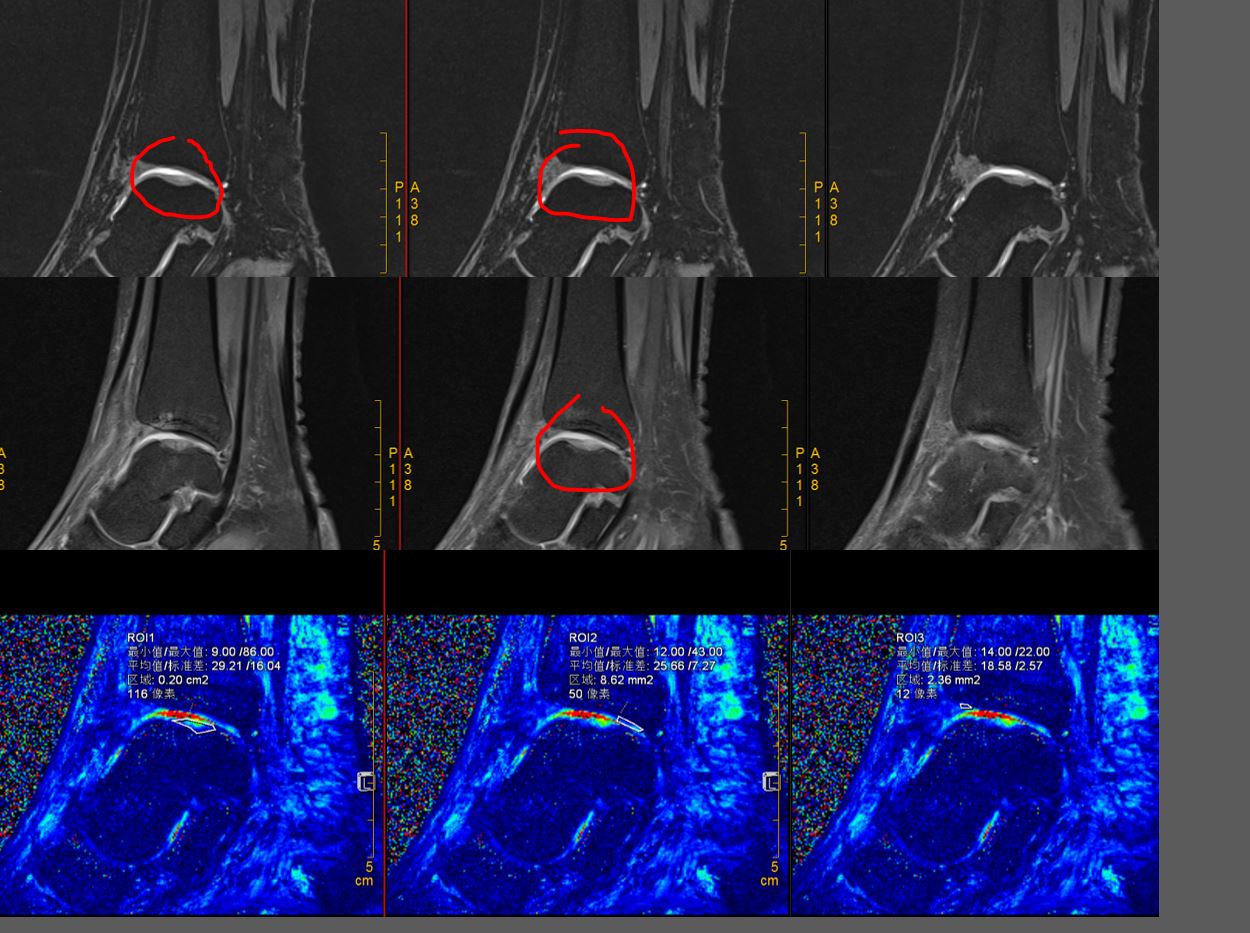

术后康复及复查,术后严格康复计划,6周内避免负重,被动活动度练习,6周逐渐恢复负重行走,术后6月恢复活动。复查核磁了解软骨再生情况。

(距骨软骨损伤区域已经由再生的软骨修复完整)